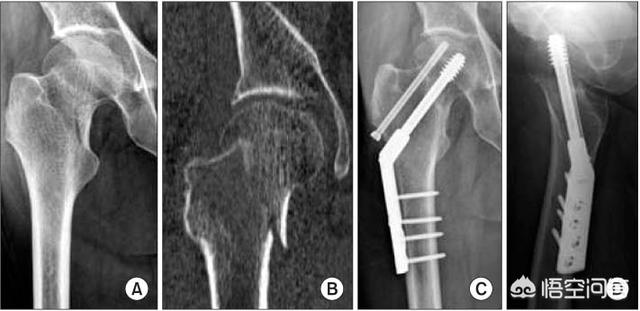

首先我们说一下骨折类型,骨颈骨折呢,我们一般来讲可以分为三种骨折类型,一种叫做头下型骨折,一种叫做经颈型股的,还有一种叫做基底部骨折。这种分型主要是跟骨折线距离股骨头的远近有关系。头下型骨折是离头最近的,经颈型骨折是中间部分,那么基底部骨股骨头最远。离头越远,那么坏死的可能性越小,离头越近坏死的可能性越大。

股骨颈骨折无论是采用了手术的治疗的方法,还是没有采用手术治疗方法。复位都是很重要的。

首先复位的时候骨折端的对合一定要非常的好,这样的话不仅可以促进骨折端的一个叠加愈合,还可以使得骨折端不露出股骨颈主干以外,刺到周围的血管。

另外在复位的时候,一定要动作轻柔,不能够活动范围太大,不然的话又会产生术中的副损伤,原来没有断的血管也可能在复位过程中被刺破。